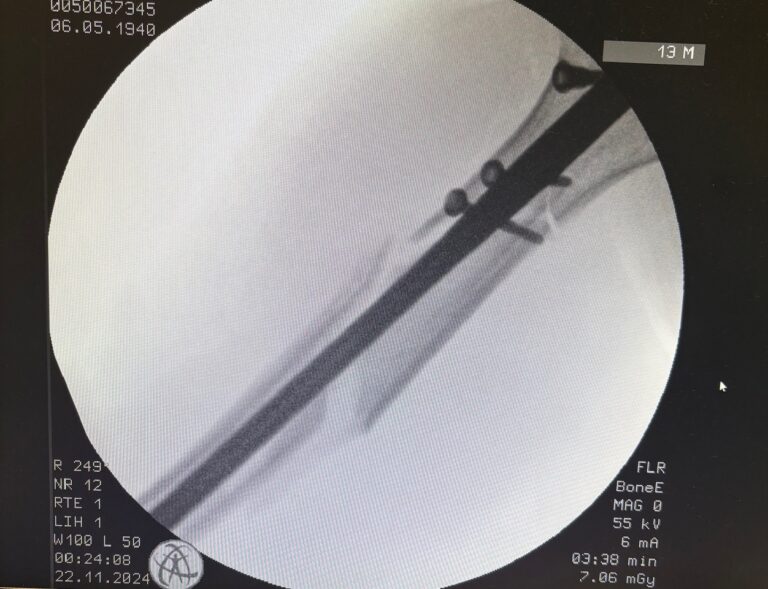

Χειρουργική

- Πλάκες, βίδες, ήλοι

- Ενδείκνυται σε ασταθή ή ανοικτά κατάγματα